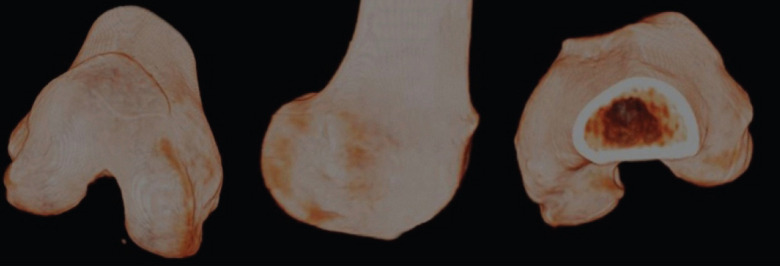

简介:屈曲期间的慢性髌骨脱位是一种罕见的与股骨发育不良和动态髌骨畸形相关的疾病。股前肿块的存在导致了机械冲突。病例报告:我们报告一例年轻成人慢性髌骨脱位膝关节屈曲期间,与髌股发育不良,前隆起,和外侧松弛。结论:治疗方法为股前远端减截骨联合髌股内侧韧带重建。术前和术后的文献资料以及影像学证实了不稳定性的矫正。

Introduction: Chronic patellar dislocation during flexion is a rare condition associated with femoral dysplasia and dynamic patellar maltracking. The presence of an anterior femoral bump contributes to the mechanical conflict.

Case report: We report the case of a young adult with chronic patellar dislocation during knee flexion, associated with patellofemoral dysplasia, anterior bump, and lateral laxity.

Conclusion: Treatment consisted of a distal femoral anterior subtraction osteotomy combined with medial patellofemoral ligament reconstruction. Pre- and post-operative documentation as well as imaging demonstrate the correction of the instability.